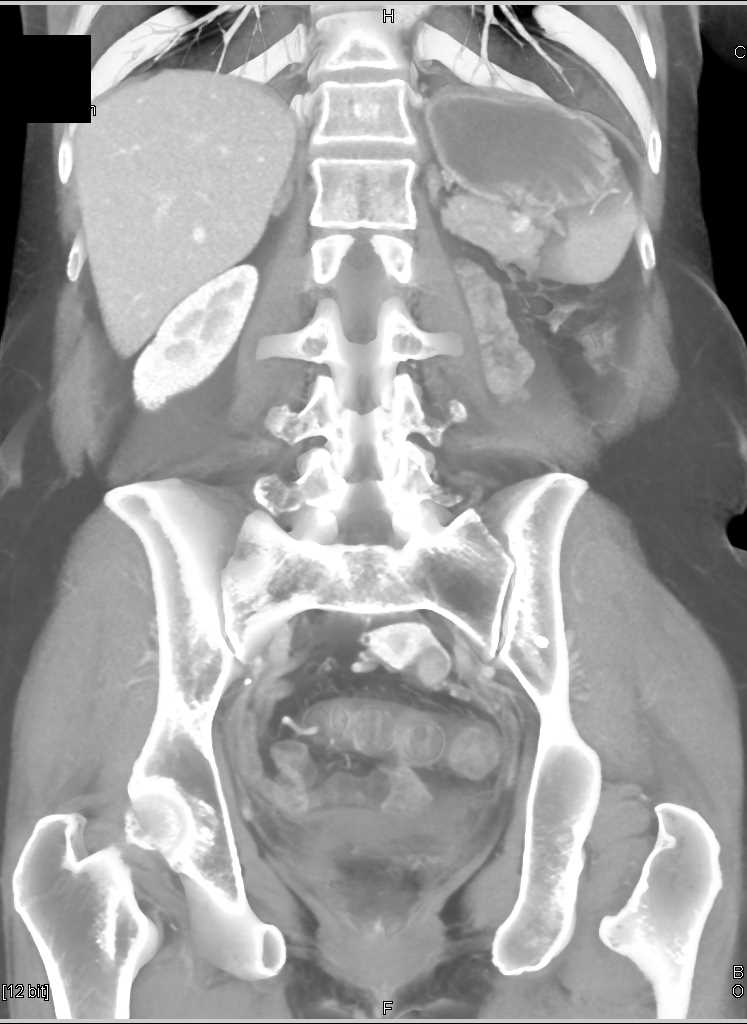

Renal Cell Carcinoma is a Solid Mass